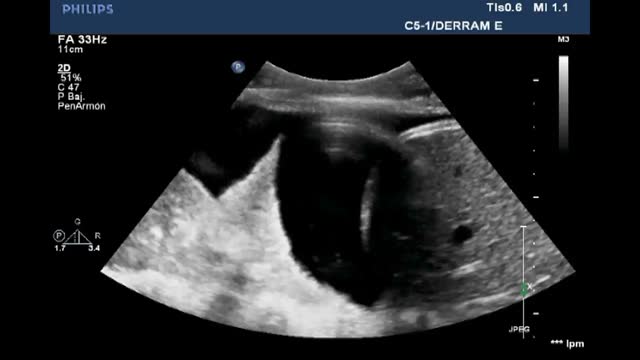

Pleural effusion (PE)Ultrasound assesses the volume (detecting millimetric magnitudes) and the characteristics of PE, guiding the site of puncture for evacuation of the effusion when needed. For this purpose, we ideally use a low-frequency convex probe (2.5-5 Hz), which sacrifices resolution in favor of greater ultrasound wave penetration capacity, reaching more in depth and visualizing the diaphragm and liver or spleen, and their relation to the lung parenchyma.

With the patient in the supine position, we place the probe on the mid-axillary line and locate the fundamental reference of the study: the diaphragm. All anechoic images above the diaphragm correspond to the chest cavity (pleural fluid). In contrast, such images located below the diaphragm correspond to the abdominal cavity (ascitic fluid)(Video 10).

Jellyfish sign: In the presence of a significant amount of intrapleural fluid, the underlying lung collapses, and the parenchyma exhibits a static air bronchogram. The atelectatic lung is contained within the PE and in the lower zone appears floating freely within the fluid, generating the characteristic movement of the jellyfish sign (Video 12).